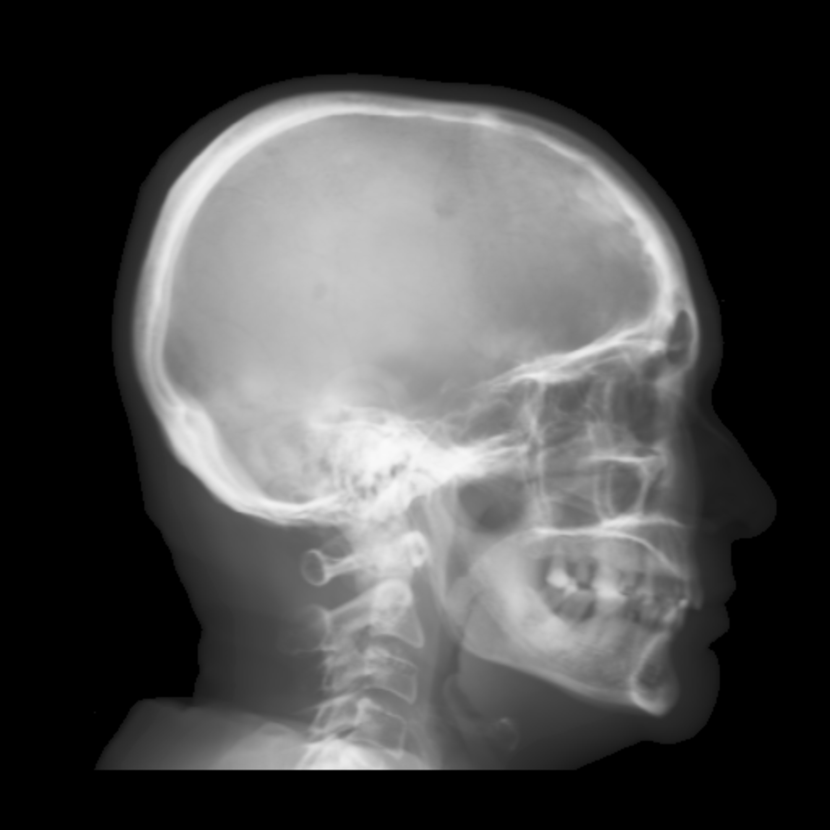

Refer to caption

(a) Real cephalogram

(b) Synthetic cephalogram

(c) Plot of samples and sigmoid curves

Fig. 2: Image contrast difference between real conventional cephalograms and RayCast synthetic cephalograms: (a) a real cephalogram example; (b) a RayCast synthetic cephalogram example; (c) the plot of samples between RayCast synthetic cephalograms and real cephalograms with an original sigmoid curve (red) and our proposed modified sigmoid curve (blue).

In Fig. 2, one real conventional cephalogram example and one example of 𝒈𝒈\boldsymbol{g} are displayed, where evident image contrast difference between these two images is observed. It is because the X-ray films used in conventional cephalograms have the special nonlinear optical property that the characteristic curve between optical density and logarithmized X-ray exposure has a sigmoid-like shape [42]. According to the Lambert-Beer law, the logarithmized X-ray exposure is equivalent to the attenuation integral. It indicates that the intensity relation between the desired cephalogram and the attenuation integral image 𝒈𝒈\boldsymbol{g} should also exhibit a sigmoid-like curve. Therefore, to make the image contrast of synthetic cephalograms similar to conventional cephalograms, a sigmoid intensity transform is necessary.